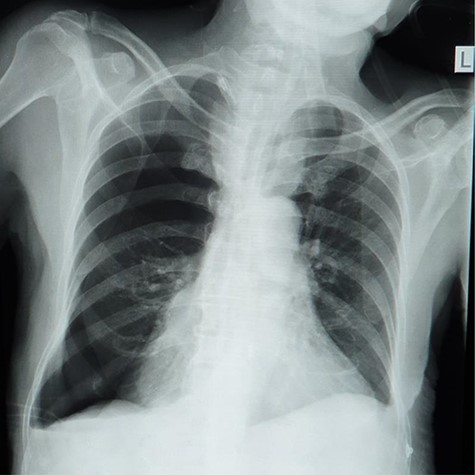

Plain abdominal X-ray (supine) showed grossly dilated large bowels (Fig. 1), and a chest X-ray showed a right-sided pneumothorax, which was managed by a thoracostomy tube (Fig. 2).

Chest X-ray showing right-sided pneumothorax with thoracostomy tube.